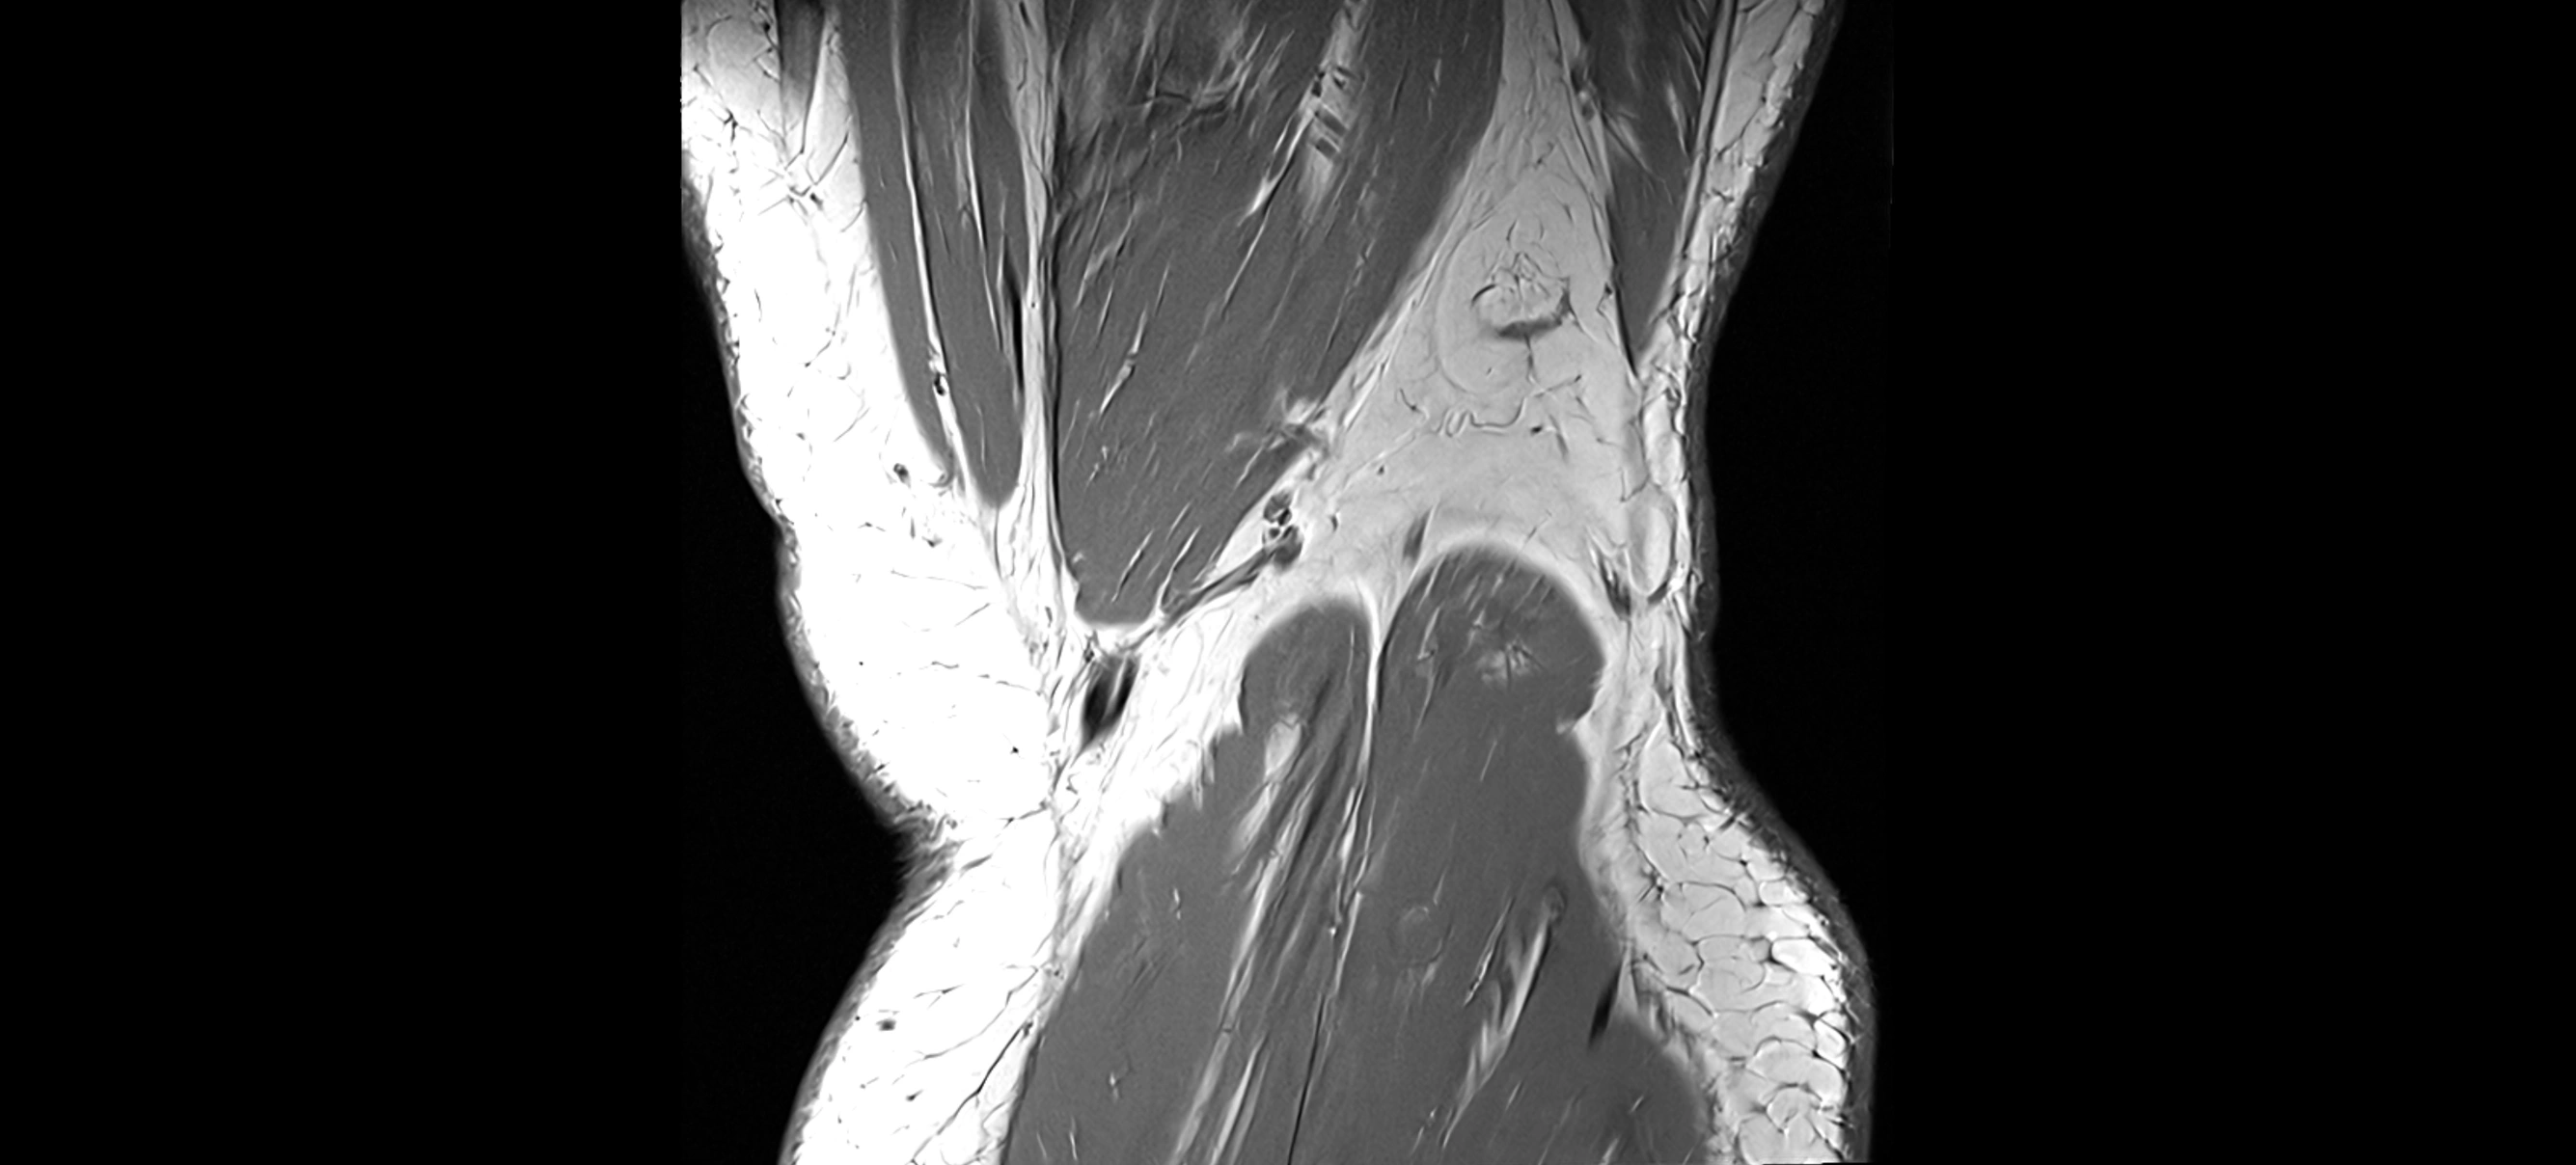

MRI images

image